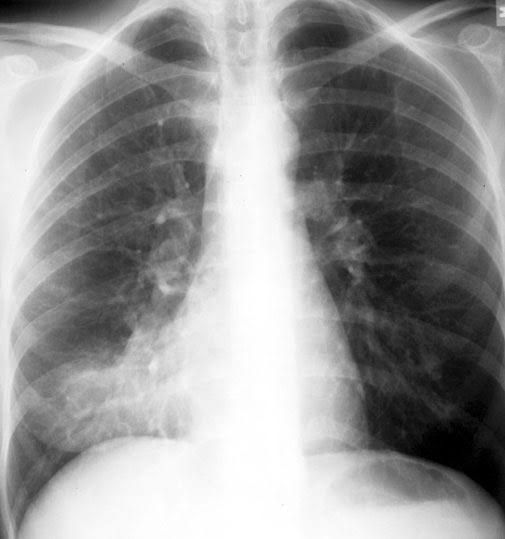

Typical Bacterial Pneumonia, also known as lobar pneumonia, is a type of community acquired pneumonia caused by Streptococcus Pneumoniae (most common), Staphylococcus aureus, Hemophilus influenza and Klebsiella. In children most of bacterial pneumonia is caused by pneumococcus. Symptoms are sudden in onset, productive cough, dyspnea and chest tightness. On examination there is bronchial breathing, a dull percussion note, increased vocal fermitus and egophony. On chest x-ray there are consolidations in one lobe.